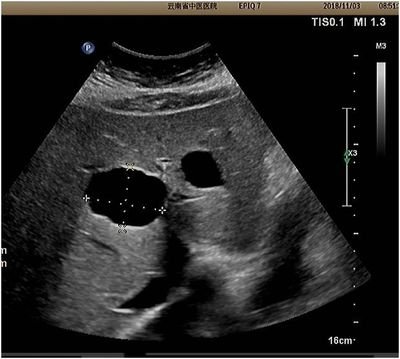

B超上看到的肝囊肿

肝囊肿因生长缓慢可长期或终身无症状,常在B超检查时偶然发现。其主要临床表现随囊肿位置、大小、数目、有无压迫邻近器官和有无并发症而异。单纯性肝囊肿相对少见,发病女多于男,男女之比为1∶4。约20%患者有症状,最常见的首发症状为腹围增大,其初发症状可始于任何年龄,但多发生在20~50岁。